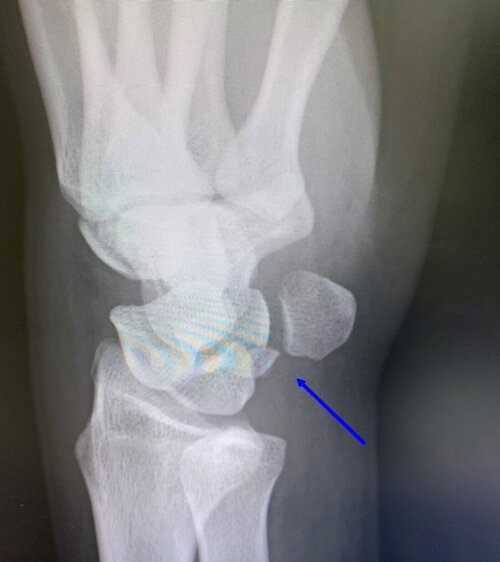

アイスホッケーのプレー中、相手と接触しフェンスに左手から激突後、

激痛と共に手首を動かせなくなったと御来院。

左上肢をダラーンとしていても痛く、受傷時は吐気がするほど痛かったそうです、、、

いつものようにしっかり問診、触診を行ったところ、

この状態は即刻、提携医にてレントゲン検査ですね、、、

レントゲンの結果は「三角骨骨折」

手首の手根骨、小指側の骨の骨折ですね。

舟状骨、月状骨の骨折は多々ありますが、

三角骨の骨折は珍しいタイプでございます。

まずは骨癒合が診られるまで、しっかりとシーネで固定しながら、

骨癒合促進のため、マイオパルス(MYO PULSE)という、

特殊な治療器で治療していきます。